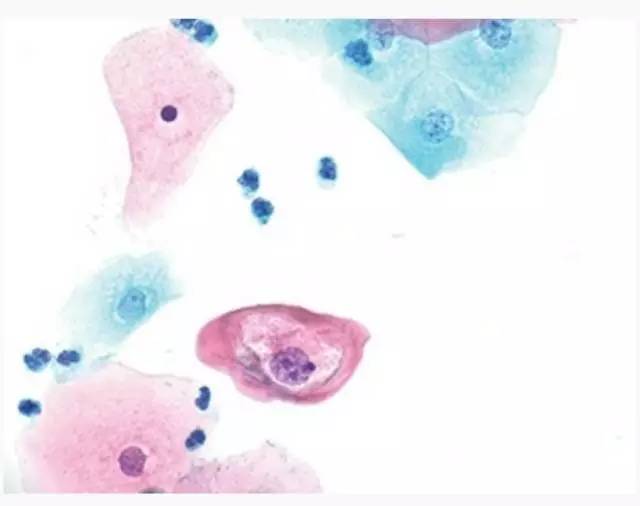

在Bethesda系统中,LSIL是一类以HPV感染为主要特征的病变。经典的LSIL表现为中、表层的鳞状上皮细胞增大,核染色质浓染,核轮廓不规则以及核周胞浆透亮的病变,后者被称为挖空细胞样改变(图1)。图1-4是细胞学检测中明确的LSIL病变。据报道,在所有细胞学检测中,LSIL占1.3-2.5%,在液基细胞学中所占比例最高。已证明在LSIL中55-89%的女性呈高危型HPV阳性(hr-HPV),在非典型鳞状上皮细胞,不能明确意义/低级别鳞状上皮内病变的分流检测(ALTS)中已证实有83%的LSIL呈现高危型HPV阳性。随着常规高危型HPV联合检测的开展,在LSILs中30岁以下的女性高危型HPV阳性率(88.8%)显著高于年长组(30-39岁为80.1%,≥60岁为77.2%)。此外,在LSIL患者中的组织学CIN2以上病变的检出率在高危型HPV阳性组和阴性组中分别为14.5%和3.7%。

图1. 典型的挖空细胞 (600×) 核周空泡及核变大

图2. LSIL 细胞团 (600×) 核增大及深染,HPV感染的细胞质表现,而非LSIL所必需的

图3. LSIL 细胞团(600×) 核大,嗜酸性胞浆,无核周空泡

图4. 少部分LSIL细胞(600×) 核周空泡, 双核形成,轻微增大的核